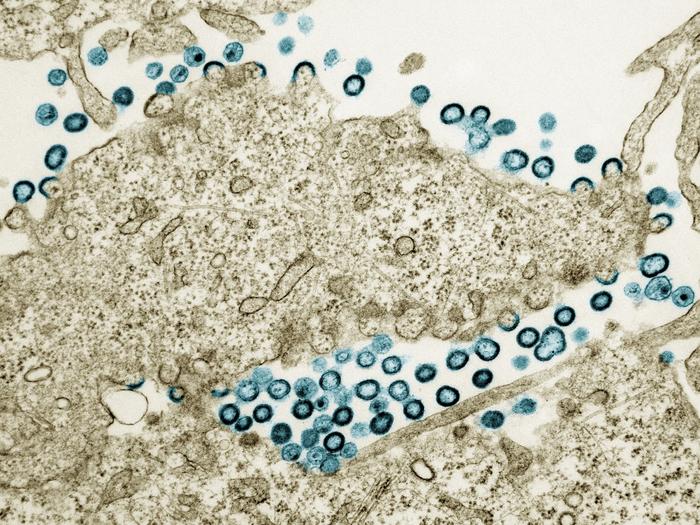

Exploratory analysis associates HIV drug abacavir with elevated cardiovascular disease risk in large global trial

Current or previous use of the antiretroviral drug (ARV) abacavir was associated with an elevated risk of major adverse cardiovascular events (MACE) in people with HIV, according to an exploratory analysis from a large international clinical trial primarily funded by the National Institutes of Health (NIH). There was no elevated MACE risk for the other antiretroviral drugs included in the analysis. The findings will be presented at the 2024 International AIDS Conference (AIDS 2024) in Munich, Germany.